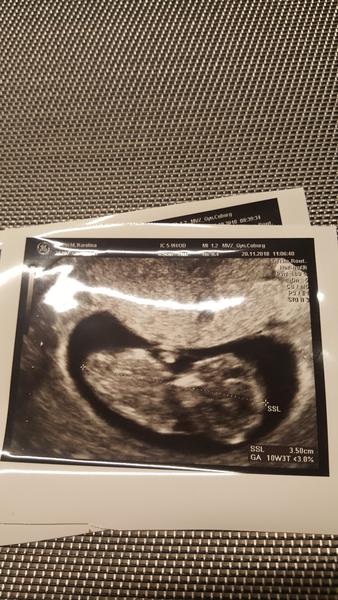

Ahoj holky, hlásím, že máme srdíčko, odpovidame opožděné ovulaci o asi 4 dny, což vím, že ji mám později než v půlce cyklu, takže vše zatím v pořádku😍, příště jdu do poradny až za tři týdny 11.12., nevím, jak to vydržím 🙈😅 a budou brát krev na 1.screening, snad se bude mimčo vyvíjet správně a tentokrát to nevzdá 😊 a na fotce vám představuji naší miminkovskou čmouhu 😎 já bych fotku ještě nebrala, ale manžel chtěl mimčo vidět 😀 mám velkou radost.

@veronikadriana jo, povyrostl za měsíc o 3cm, tak si myslím, že dobrý a že už teď je šikula🙂)).